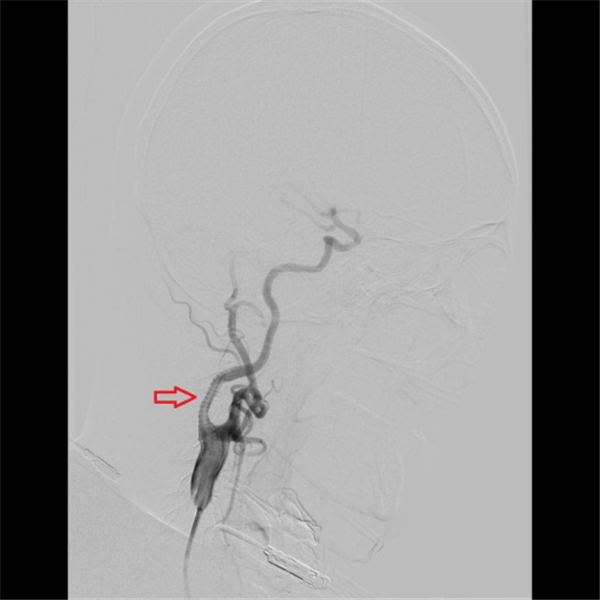

当天,老杜就顺利入住北京燕化医院,第三天就安排了介入手术:在右侧腹股沟局麻之后,穿刺股动脉插管到主动脉,再选择到右侧颈动脉造影,可见右侧颈内动脉重度狭窄、几近闭塞(上图红色箭头)。

确定狭窄部位之后,在微导丝的引导之下,小心的将保护伞(上图红色箭头之间)置于狭窄段远端,以阻拦可能脱落的斑块,避免术中脑梗塞的发生,手术结束之后再将保护伞回收。

之后用球囊扩张右侧颈内动脉(上图红色箭头所示为狭窄部位)。

球囊完全扩张后,可见狭窄部位血流通畅(上图红色箭头所指)。

球囊完全扩张之后,动脉狭窄消失(上图红色箭头之间)。

术后再次造影显示,右侧颈内动脉支架位置好,膨胀充分,血流通畅,颅内血管未见异常(上图红色箭头所示)。